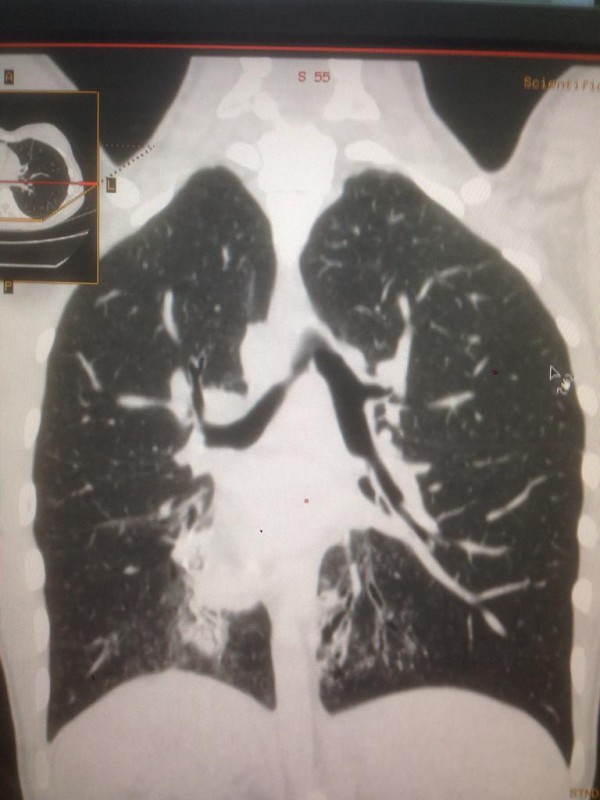

"Это генное нарушение. При нем у людей нездоровы дыхательные пути. Характерные черты: синклиты, бронхоэктазы и зеркальное расположение органов. Люди с таким диагнозом испытывают слабость, температуру, боль в ушах, одышку, хрипы. Поэтому пациенты с раннего возраста проходят лечение. Состоят на диспансерном учете у детского пульмонолога. В год они получают около пяти раз стационарное лечение, находятся под наблюдением врачей, пропивают антибиотики", - говорит собеседник.

Синдром Зиверта-Картагенера. Снимок предоставлен Сундетом Саргеловым